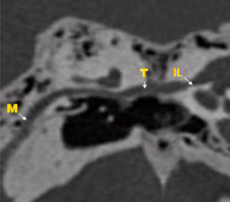

La evaluación mediante tomografía es fundamental para identificar los focos otoscleróticos, principalmente en la ventana oval a nivel de la fissula antefenestran, la cual es un surco que se localiza entre la ventana oval y el proceso cocleariforme. En la fase otospongiótica o activa de la otosclerosis, se pueden observar áreas hipodensas en el hueso, mientras que en la fase inactiva otosclerótica, se observara hueso compacto que puede afectar progresivamente la platina del estribo, provocando la fijación de este.

El grosor normal de la ventana oval se establece en 1.64 mm; valores superiores a 3 mm son considerados compatibles con otosclerosis. En un bajo porcentaje, alrededor del 10%, se presenta un subtipo retrofenestral, que afecta la cápsula ótica y puede resultar en desmineralización, lo que se clasifica como "otosclerosis muy avanzada", según lo definido por House y Sheehy.93 A continuación, se detallan las diferentes clasificaciones relacionadas con esta patología (Tabla 2 y 3).

Tamaño del nicho de la ventana oval: Valores de 1,4 mm se toma como límite inferior de la normalidad. Valores menores se asociaban con un riesgo mayor de tener dificultades técnicas durante la cirugía del estribo. Debe descartarse una otosclerosis obliterativa (Fig. 4-5). |

Figura 4. Vista de la ventana oval en un corte coronal del oído medio |

Figura 5. Ventana oval obliterativa de oído derecho en un corte coronal de oído medio |